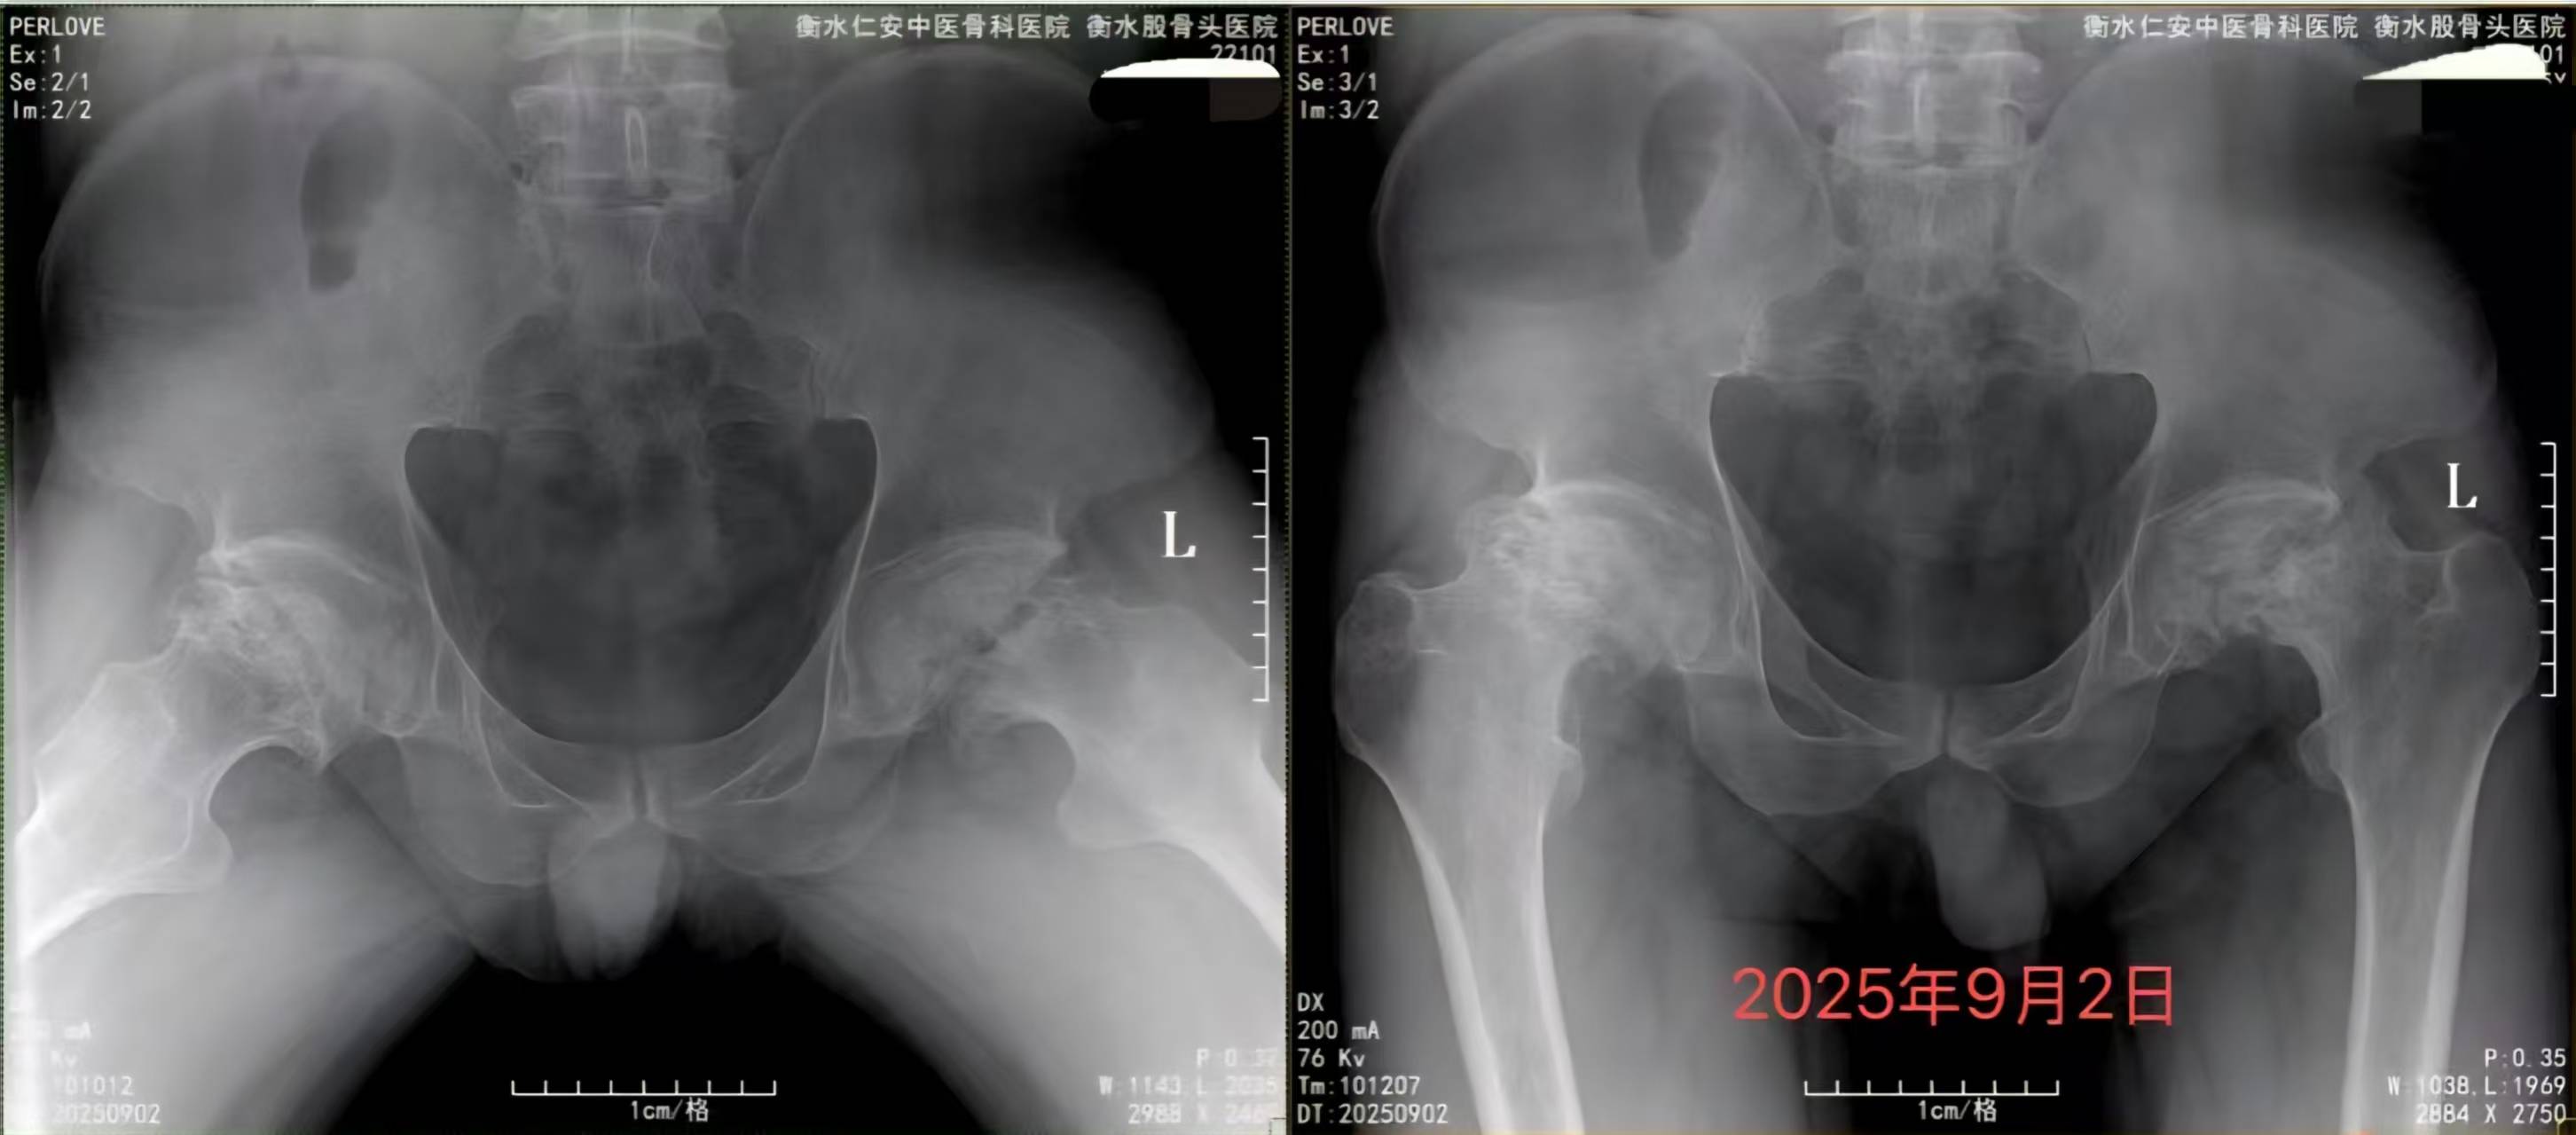

情境再现 男性,71岁,身高169.5 cm,体重71.5 kg,BMI 24.9 kg/m²。因前列腺癌行全麻下机器人辅助腹腔镜根治性前列腺切除术。 既往合并双侧肾上腺肿瘤(非功能性)、支气管哮喘、